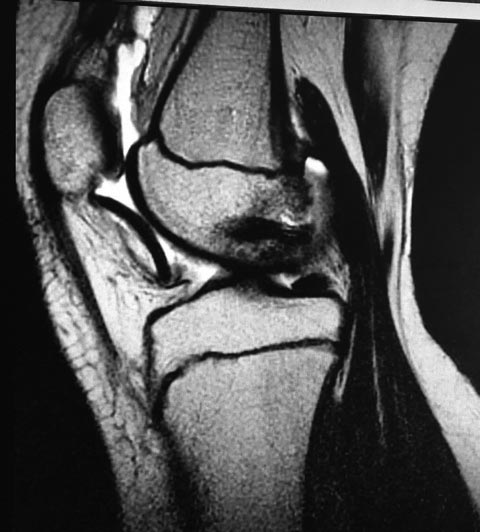

Девочка10 лет. Травма 1 месяц назад – упала на горке. Лечилась консервативно. По данным МРТ имеется остеохондральный дефект наружного мыщелка бедренной кости и свободный костно-хрящевой фрагмент размером 3 см. в диаметре. Девочка 10 лет. Травма 1 месяц назад. По данным МРТ имеется остеохондральный дефект наружного мыщелка бедренной кости и свободный костно-хрящевой фрагмент 3 см в диаметре.

Girl 10 years old. She fells on the hill 1 month ago. Conservative treatment. According to the MRI she has osteochondral defect of external femoral condyle and free osteochondral fragment size of 3 cm. in diameter. Optimal fixation if possible?